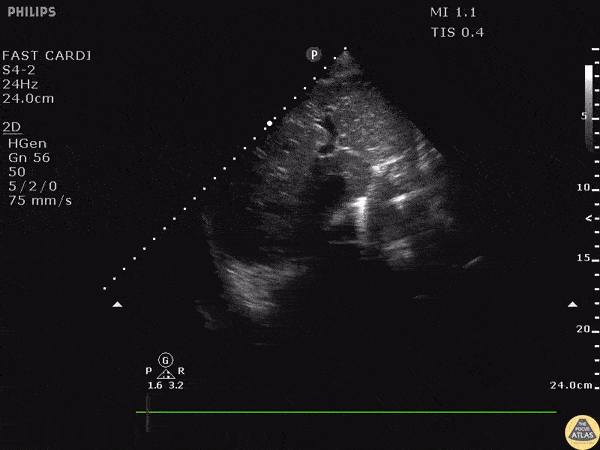

Trauma - Gunshot Wound Foreign Body

Subcostal window in a patient with a gunshot wound revealed a hyperechoic structure with strong comet tail reverberation artifact. These findings are consistent with a metallic foreign body, such as a retained bullet in this patient. Visit the original post for a labelled image. Image courtesy of Robert Jones DO, FACEP @RJonesSonoEM Director, Emergency Ultrasound; MetroHealth Medical Center; Professor, Case Western Reserve Medical School, Cleveland, OH View his original post here